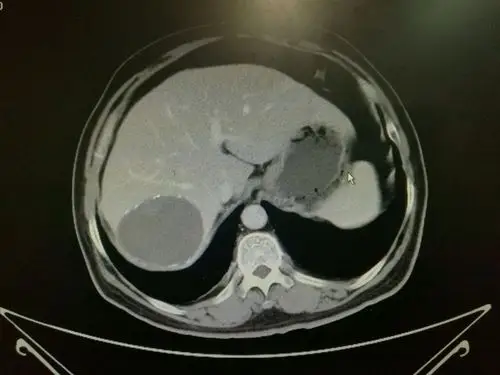

每周诊疗笔记之肝包虫病外科治疗